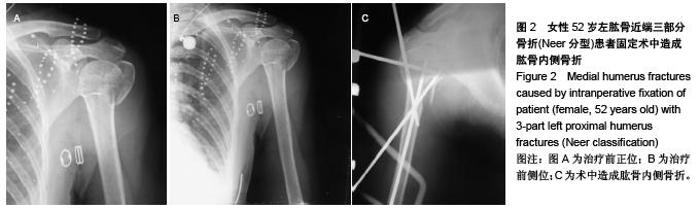

Novel closed intersection nailing external fixation repairs proximal humerus fractures: 6-month follow-up

Huang Hai-jing, He Jin-quan, Wang Jie, Jin Hong-bin. Novel closed intersection nailing external fixation repairs proximal humerus fractures: 6-month follow-up[J]. Chinese Journal of Tissue Engineering Research, 2015, 19(48): 7795-7800.